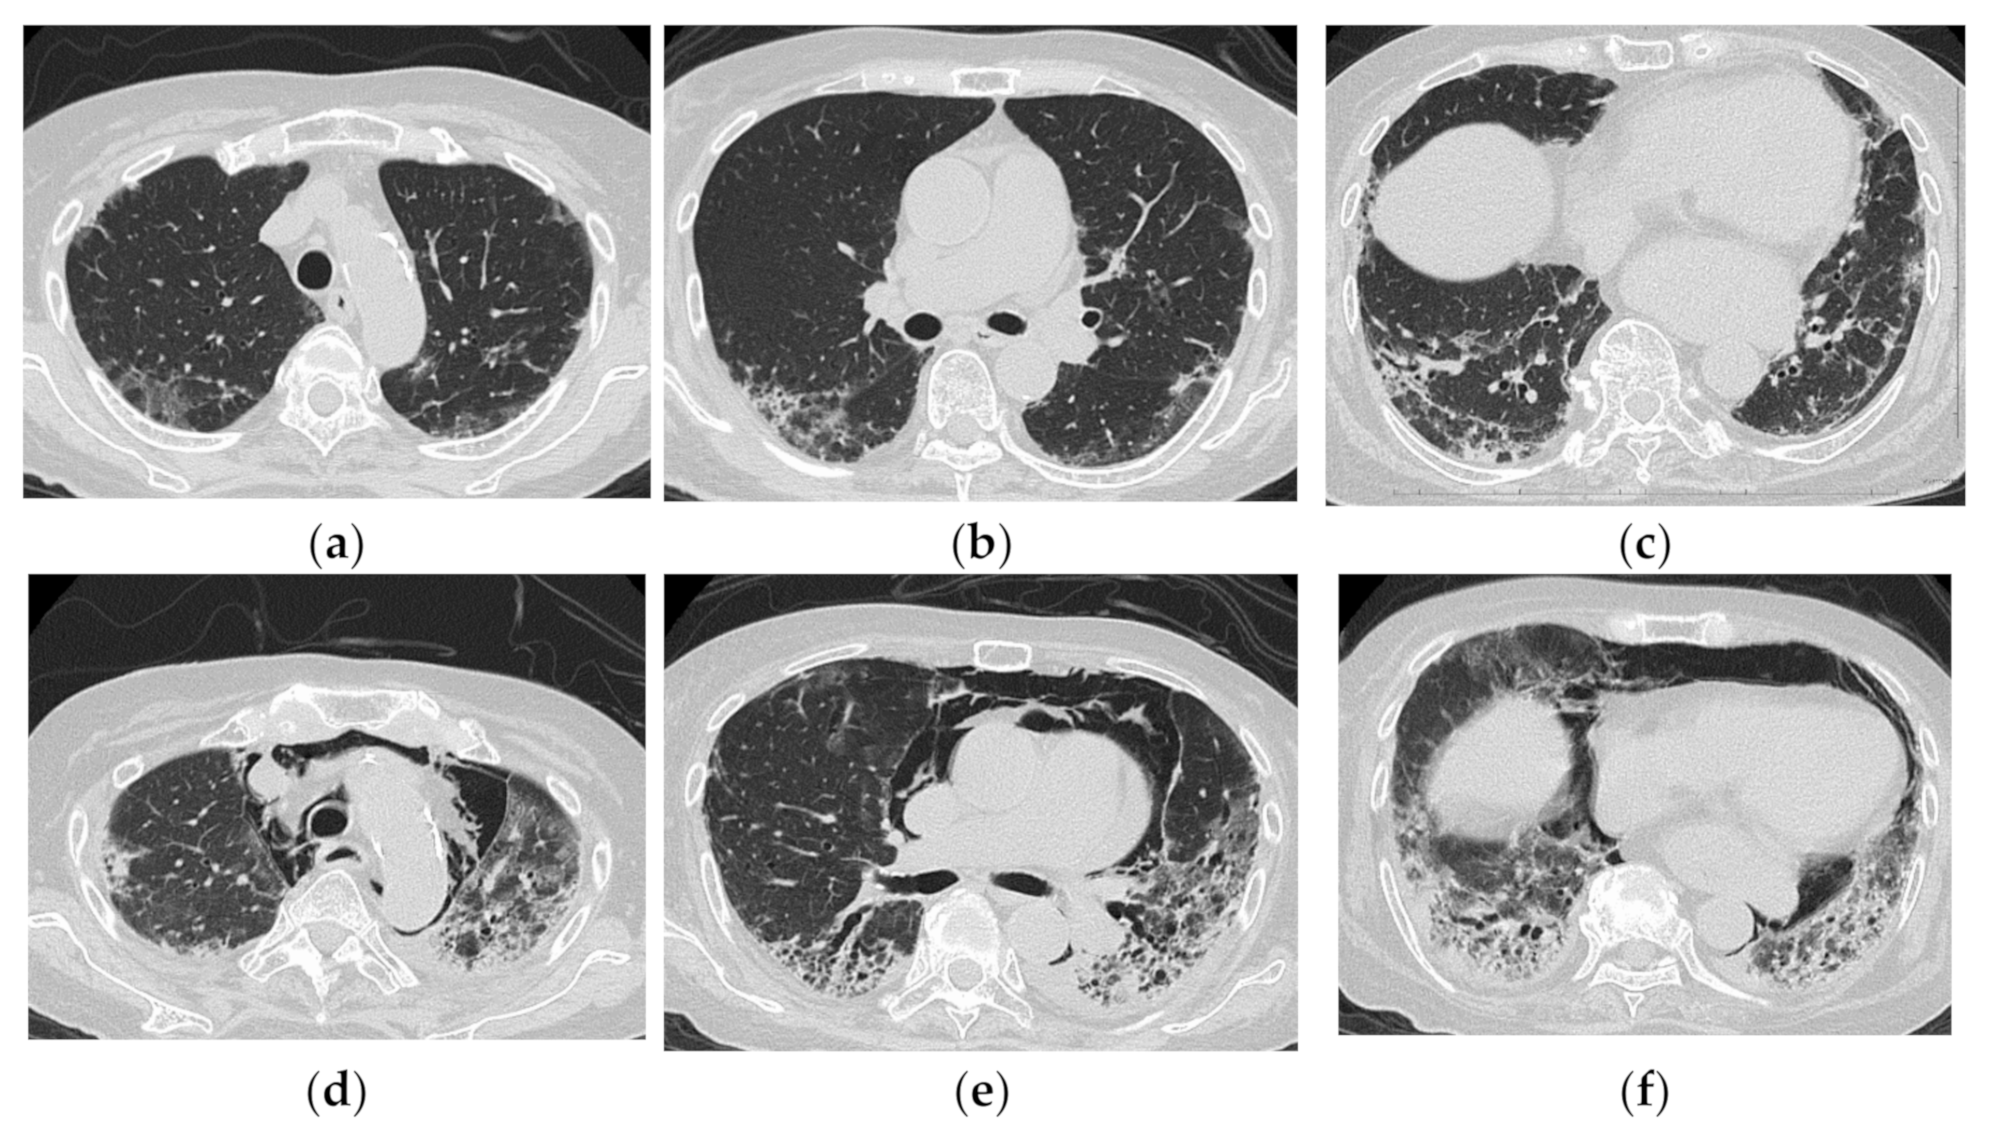

3.1. Anti-Aminoacyl tRNA Synthetase Antibody (Anti-ARS Ab)

HRCT Findings of Patients with Anti-ARS Ab

3.2. Anti-MDA5 Antibody (Anti-MDA5 Ab)

HRCT Findings of Patients with Anti-MDA5 Ab